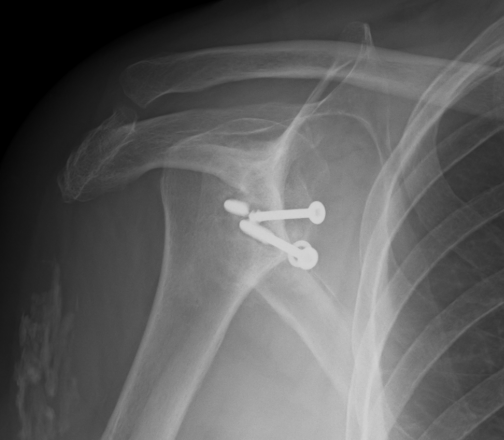

Nonunion with failure of fixation / recurrent instability

Nonunion with failure of fixation

Latarjet nonunion with hardware failure and displacement of coracoid fragment

Options

- distal tibial allograft

- iliac crest / modified Eden-Hybinette procedure

www.boneschool.com/distal-tibia-allograft